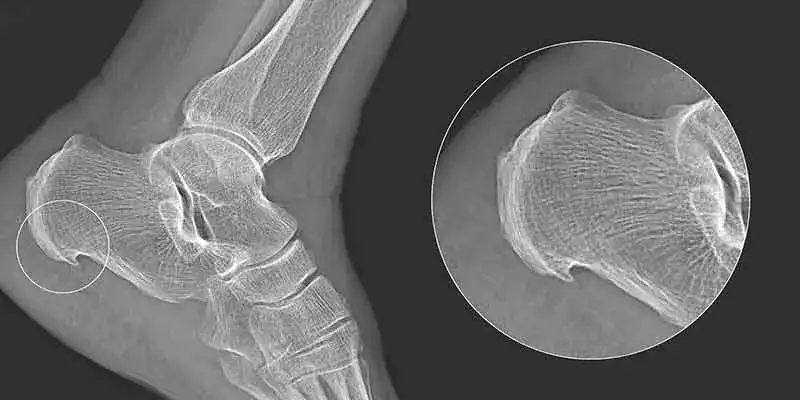

Ostroga piętowa: objawy i skuteczne metody leczenia

Ostroga piętowa to jedna z najczęstszych przyczyn bólu pięty. Objawia się ona ostrym bólem, szczególnie podczas pierwszych kroków po wstaniu z łóżka lub po dłuższym siedzeniu. Ból może się nasilać podczas chodzenia lub stania. Warto zwrócić uwagę na objawy, aby szybko zareagować.